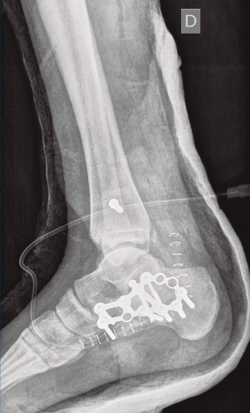

Bajo isquemia se realiza un abordaje lateral en L ampliado y se expone el calcáneo. Se trató de realizar una reducción abierta empleando un clavo de Steinmann (maniobra de Westhues), lo cual no se consiguió hasta la realización de un alargamiento percutáneo del Aquiles. Se comprobó bajo escopia la correcta reducción tanto de la fractura del calcáneo como de la luxación al nivel del tobillo. Se realizó una fijación con una placa de calcáneo, con 7 tornillos de esponjosa de 4 mm de diámetro (2 de ellos bloqueados) tras la reducción de la carilla posterior con un tornillo a compresión de 3,5 mm.

A continuación, pasamos a realizar un segundo abordaje lateral, respetando una separación suficiente para minimizar el riesgo de necrosis cutánea, a través de la cual se reparó la rotura del complejo ligamentoso lateral y se fijó la sindesmosis con un tornillo transindesmal de 4 mm de diámetro tras comprobarse bajo escopia la lesión al nivel de la articulación tibioperonea distal. Se inmovilizó mediante una férula posterior a 90°.

Figura 10. Control radiográfico posquirúrgico, lateral.